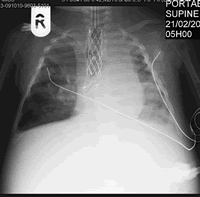

During Leah's stay in hospital from 15 December 2008 she's been on the ventilator, getting tube feeding and numerous medications and antibiotics. We could never have imagined that Leah would have been in the hospital for so long.

No one can prepare you for seeing your baby lying in a bed with multiple tubes and drips connected to her, you not being able to even pick her up because of the ventilator.

On Tuesday 28 April 2009 they extubated Leah ........ and the trachea stayed open!! The doctors watched in disbelieve as Leah was breathing on her own, awake and fully aware of what was going on around her. All the nurses came to see how she was doing and was also amazed at how well she was doing. I was able to hold her again on the thursday. She's lost a lot of weight and is now weighing 4.30kg. She was struggling to breath and not doing to well. They had to put the ventilator back on. They decided to take her into theatre that evening for a bronchoscopy to see if there is another narrowing of the trachea, there was and they had to do another balloon dialatation. After that a hole appeared in her lung. She deteriorated during the night and had to be taken into theatre at 04h00 on friday morning. They had to operate and close the hole. This was a big shock to us as we thought we were on the way out of the hospital. |

Leah is doing well and stable after the operation. They will keep her sedated for a few days and start with the weaning process as soon as she is doing well enough.

Leah is not absorbing any of her feeds at the moment and her tummy is very extended. They have placed a deudenal tube in (a tube through her nose that goes through the tummy into the deudenum) and they then give 2ml milk every hour. It is partially digested milk helping with the absorbsion. She is on full ventilation and under constant sedation. She is not allowed to wake up and move around. They want the ventilator tube to be an internal stent to the trachea, thus meaning that the tube can't move.